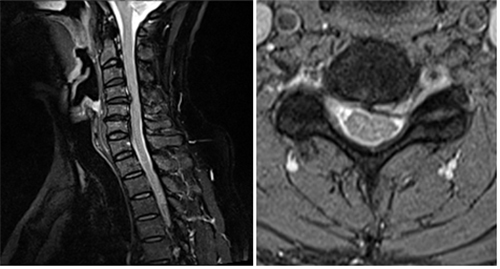

척추의 진단은 MRI 뿐만 아니라 환자와의 충분한 인터뷰와 섬세한 진찰을 토대로 초음파, 신경 검사, CT, MRI, 다른 과 전문의와 협진 등 양한 검사 방법을 통해 체계적으로 확정된 정확한 진단이 필수입니다. 척추의 질환과 치료는 고가의 시술이나 수술이 만병 통치약이라 할 수 없으며 약물치료, 물리치료, 주사요법, 통증 클리닉 등 타 과와의 협진을 기본으로 하여 수술은 선택적으로 고려된 각 환자에게 특화된 입체적인 치료이어야 합니다.

이러한 디스크는 스프링처럼 충격을 완화 시키고 척추 뼈가 밀리지 않고, 척추 뼈들이 부딪히지 않도록 보호해주는데 나이가 들어감에 따라 수핵의 수분함량의 감소로 탄력성이 떨어지면서, 경우에 따라 나쁜 자세나 사고 등 외부적인 자극이 가해져 경추 디스크가 밀려나 주위 신경근을 자극하여 통증을 일으키는 것을 `목디스크`이라 합니다.

목디스크의 증상은 만지면 전기 오듯 더 심한 저린 느낌, 둔한 느낌 등의 감각이상이나 쥐는 힘이 떨어져 물건을 놓치거나 팔을 들어 올리기가 힘든 경우와 같은 마비증상입니다

목디스크의 치료는 보존적 치료 및 수술적 치료가 있습니다.

보존적 치료로는 침상 안정, 약물 요법, 물리 치료, 운동 요법,체중 조절, 국소적으로 마취제나 스테로이드를 압통이 있는 부위에 주사 방법등이 있습니다.

수술적 방법으로는 가장 일반적인 방법으로는 목의 앞쪽에서 디스크을 완전히 제거하고 골이식을 하는 방법이 가장 보편적으로 많이 사용되는 방법이며, 수술의 안정성이나 임상 결과 측면에서 수 십년 간의 오랜 임상 경험을 통하여 효과가 입증되어 있는 방법입니다.

두 번째로는 경추 인공디스크 삽입술을 들수 있습니다. 인공 디스크란 기존의 손상된 디스크를 제거하고 이를 인공물로 대치하는 방법입니다. 수술 방법은 일반적인 전방 고정술과 비슷하나 수술 후에도 그 부위의 운동을 유지시킬 수 있어 유합술로 인해 초래될 수 있는 인접마디 변성을 막을 수 있다는 큰 장점이 있습니다.

하지만 비용이 상대적으로 비싸고, 뼈의 퇴행성 변화가 심한 경우에는 사용할 수 없다는 단점이 있으며, 전세계적으로 임상 경험이 상대적으로 짧아 장기적인 임상 결과는 아직 연구 중입니다.